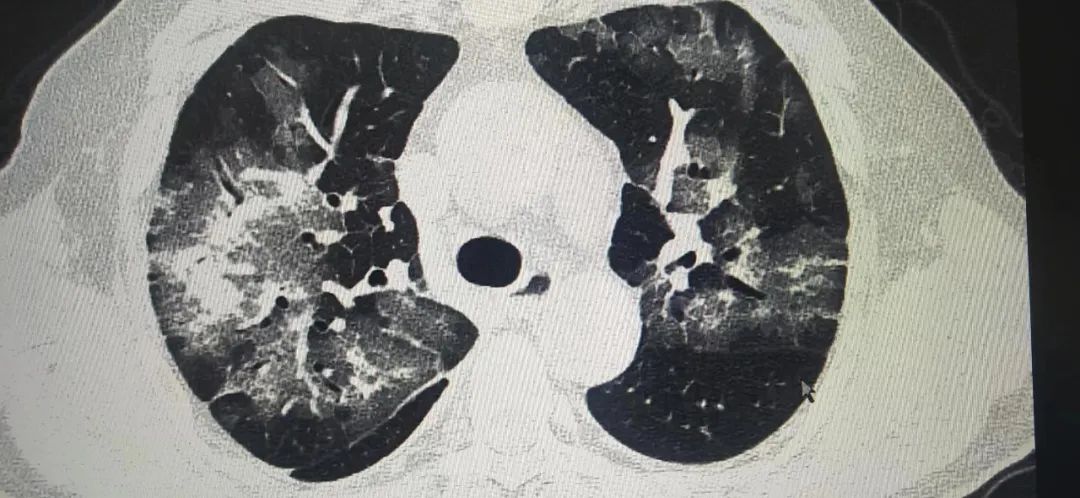

胸片只能做一个初步的粗略判断,付建英介绍,胸部CT则以1毫米为一层的断面,精准展现患者的肺部影像,就连软组织、骨骼场都能看得一清二楚,细微病灶也不会漏诊。在高分辨率的大尺寸屏幕上分析患者CT,即使是较小的磨玻璃样结节,都逃不过胸部CT的慧眼。

据陕西冶金医院医学影像科付建英主任讲,目前新闻各种报道奥密克戎感染后大部分为无症状或轻症,我自己接诊的患者中一部分有出现肺部表现的患者。比如上面的病例,CT检查都是出现了肺部表现,一个人是病变局限,病变于胸膜下分布。表现为单发或多发磨玻璃样密度结节状、斑片状影。其内可见空气支气管征和血管增粗表现。另外一个则是弥漫性磨玻璃样渗出,病变进展,病灶增多、范围扩大。可累及多个肺叶,下叶居多。病灶变密实。严格意义上讲,这几个病例都倾向于类似于新冠感染后的肺部表现。随着感染人数增多,可能还会有类似的病例出现。好在这样的病例确实不多,大部分还是上呼吸道感染的症状居多,发热咽痛是最常见的症状表现,但如果出现呼吸困难,还是要到医院拍个CT的。